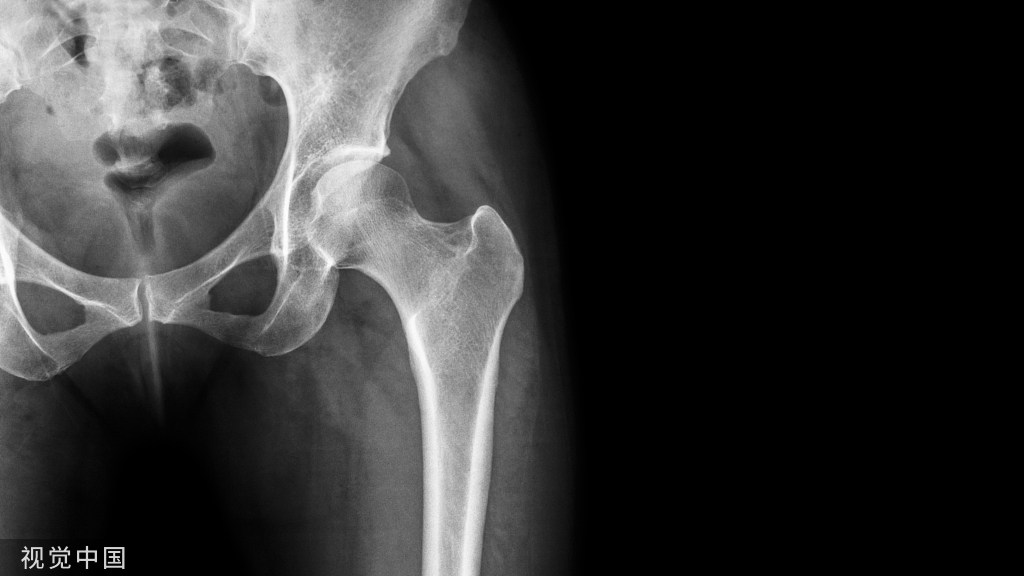

2个月后复查CBCT见充填物完好,根尖低密度暗影较前明显缩小